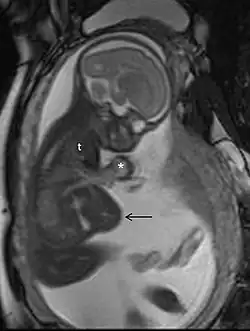

MRI is commonly used in pregnant women with acute abdominal pain and/or pelvic pain, or in suspected neurological disorders, placental diseases, tumors, infections, and/or cardiovascular diseases.[3] Appropriate use criteria by the American College of Radiology give a rating of ≥7 (usually appropriate) for non-contrast MRI for the following conditions: